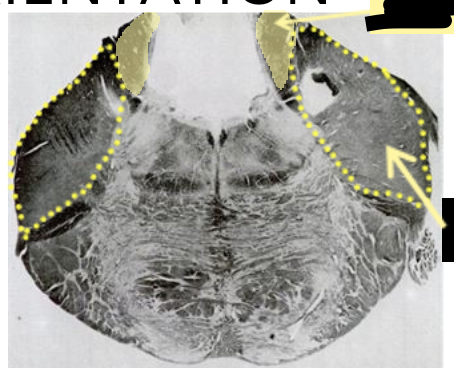

What cut of the brain stem is this?

What is this missing, which should give you a hint where it is?

Whats the shape of the rostral pons kind of resemble?